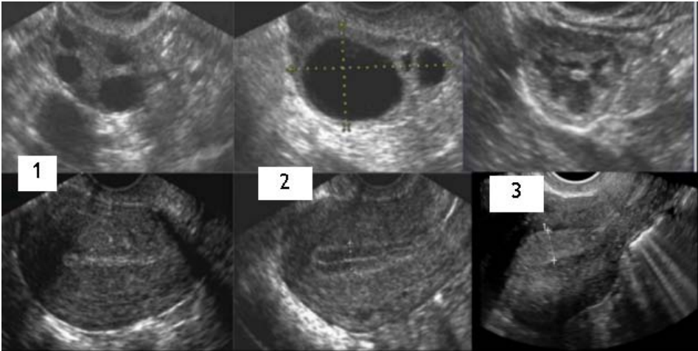

Considere a imagem abaixo:

As figuras 1, 2 e 3 correspondem, respectivamente, a que fase do ciclo ovulatório/menstrual?